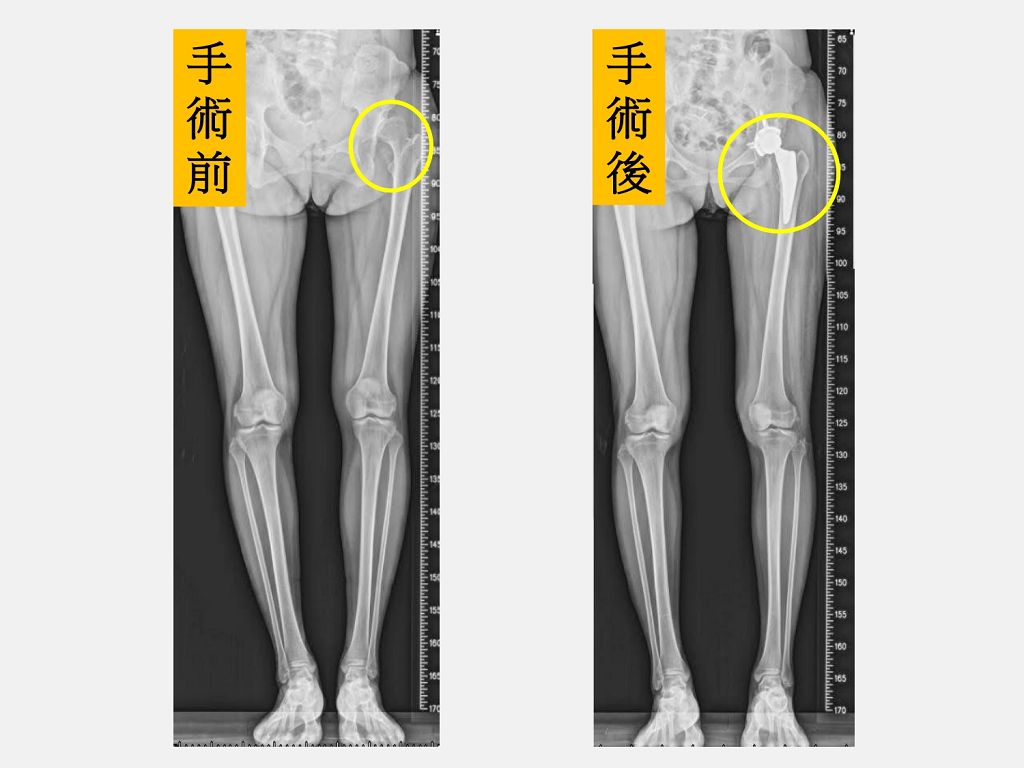

34歲的陳小姐因為左邊髖關節發育不良在幼兒園和小學時分別接受過2次髖關節截骨矯正手術。然而,在走路時卻始終還會有卡卡的感覺,運動後也常常痛到像企鵝一樣一跛一跛的。隨著小孩上小學後活動越來越多,參加活動常常讓她痛到力不從心,羨慕其他的媽媽們可以全心全意陪伴小孩成長,不想缺席卻又不得不吃止痛藥硬撐著,糾結的心情讓她鬱悶到幾乎快得了憂鬱症。陳小姐接受仁愛長庚合作聯盟醫院(大里仁愛醫院)骨科部黃贊文部長建議選擇「微創正前開髖關節置換手術」治療,經過2個月的肌肉訓練,已經幾乎恢復正常生活,計劃在小孩小學畢業後一起去日本旅行,終於重回人生軌道。

黃贊文部長表示,陳小姐因為長年疼痛和不能好好參加小孩的社團發表、學校活動讓她看起來非常憂鬱,也轉介給身心科醫師一同協助。陳小姐左側髖關節和大腿因為曾經手術2次有著長達30公分疤痕,肌肉也有明顯的萎縮,因此建議進行「微創正前開髖關節置換手術」。陳小姐在手術當天下午麻醉藥效一退,就開始練習騎腳踏車運動,陳小姐說,原本以為會很痛,但完全沒有痛的感覺,2隻腳也一樣長了,腳踩在地上的感覺非常不真實,就像是睡了一覺做了一個夢,很擔心萬一夢醒了怎麼辦?當下激動到眼角泛淚。

【台灣電報記者 玉女/ 台中報導】 34歲的陳小姐因為左邊髖關節發育不良在幼兒園和小學時分別接受過2次髖關節截骨矯正手術。然而,在走路時卻始終還會有卡卡的感覺,運動後也常常痛到像企鵝一樣一跛一跛的。隨著小孩上小學後活動越來越多,參加活動常常讓她痛到力不從心,羨慕其他的媽媽們可以全心全意陪伴小孩成長,不想缺席卻又不得不吃止痛藥硬撐著,糾結的心情讓她鬱悶到幾乎快得了憂鬱症。陳小姐接受仁愛長庚合作聯盟醫院(大里仁愛醫院)骨科部黃贊文部長建議選擇「微創正前開髖關節置換手術」治療,經過2個月的肌肉訓練,已經幾乎恢復正常生活,計劃在小孩小學畢業後一起去日本旅行,終於重回人生軌道。 黃贊文部長表示,陳小姐因為長年疼痛和不能好好參加小孩的社團發表、學校活動讓她看起來非常憂鬱,也轉介給身心科醫師一同協助。陳小姐左側髖關節和大腿因為曾經手術2次有著長達30公分疤痕,肌肉也有明顯的萎縮,因此建議進行「微創正前開髖關節置換手術」。陳小姐在手術當天下午麻醉藥效一退,就開始練習騎腳踏車運動,陳小姐說,原本以為會很痛,但完全沒有痛的感覺,2隻腳也一樣長了,腳踩在地上的感覺非常不真實,就像是睡了一覺做了一個夢,很擔心萬一夢醒了怎麼辦?當下激動到眼角泛淚。 黃贊文醫師指出,髖關節發育不良導致的髖關節炎一般好發在40至55歲,女性居多。若在兒童時期就診斷出來,可進行髖關節截骨矯正手術來促使髖關節得以正常發育;若是在成年後發現有初期的髖關節炎也可以藉由髖關節截骨矯正手術來延緩置換人工關節的時間;但若已進展到末期,治療的方式則是直接安排人工髖關節置換手術。 黃贊文醫師說,對於長期疼痛和關節沾黏、僵硬的病人,肌肉萎縮的情況會比較嚴重,如果採行需要切開臀部肌肉的傳統手術方式,在肌肉縫合後仍然需要6-8週的時間癒合,活動限制多。此外,走路的步態較不穩定。病人需要助行器和拐杖來輔助日常生活,以避免因肌肉無力而跌倒並進一步造成脫臼和骨折。 黃贊文醫師表示,該院的人工關節置換手術都會啟動「怡樂適(ERAS)手術加速康復療程」。手術當中,麻醉科醫師使用術中腦波監測儀精準控制麻醉的深度,避免因麻醉過深引發呼吸抑制、延遲清醒、頭暈和噁心嘔吐等副作用。此外,由於「微創正前開髖關節置換手術」是從肌肉間隙進入關節,對周圍的肌肉幾乎沒有破壞,術後疼痛減輕,恢復快,行走步態也較穩定,通常病人在手術當天下午即可持助行器走路,用固定式腳踏車運動。大部分病人僅需要2-4週的時間使用助行器和拐杖,不需要等待6-8週肌肉癒合的時間,即使是像陳小姐這樣肌肉萎縮嚴重的情況,經過2個月的肌力訓練也可以恢復得很好。 黃贊文醫師指出,若病人本身的骨頭有嚴重的變形、骨頭遺留有手術的鋼釘、鋼板或患有病態肥胖等,則比較不合適進行「微創正前開髖關節置換手術」。但最重要的還是提醒民眾,若有髖關節疼痛的症狀時,應儘早尋求專業醫師診斷及治療。 黃贊文部長表示,陳小姐左側髖關節和大腿曾手術有疤痕,肌肉也明顯萎縮,因此建議進行「微創正前開髖關節置換手術」。 左邊髖關節進行「微創正前開髖關節置換手術」後(右圖圓圈處),2隻腳一樣長,走路終於不再卡卡。 黃贊文部長指出,髖關節發育不良導致的髖關節炎一般好發在40至55歲,女性居多。